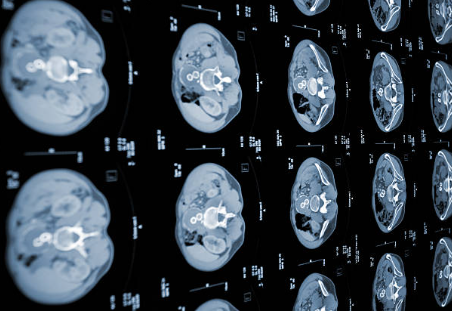

2) 영상 검사

CT 촬영 : 출혈 여부 확인합니다.

MRI 촬영 : 뇌 손상 범위 및 혈류 상태를 파악합니다.